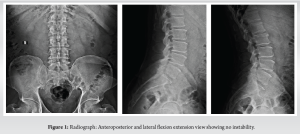

A 62-year-old male presented to the outpatient department with low back pain (visual analog score [VAS] 6/10) with left anterior thigh radiation (VAS 8/10) associated with tingling in a known case of hypertension and chronic lymphoid leukemia (CLL). On neurologic examination, gait was antalgic while the femoral nerve stretch test was positive and straight leg raising test was negative. There was no lower limb power weakness while sensations and deep tendon reflexes were intact. There was no recent history of fever, bleeding diathesis, or anti-coagulant intake. Provisional diagnosis of lumbar radiculopathy was considered. Blood investigations revealed normal platelets (133000) with raised total leukocyte count (TLC) (188810). Lumbar spine anteroposterior and lateral dynamic views had no radiological instability (Fig. 1). while magnetic resonance imaging (MRI) revealed L2–L3 inferior disc sequestration with disc desiccation compressing the exiting L3 nerve root (Fig. 2). The patient was posted for microscopic discectomy and procedure was uneventful and sequestered disc fragments were retrieved with complete decompression of the nerve root. The patient had significant improvement in radiculopathy in post-operative (VAS 1/10) and was comfortably walking the next day. Routine hemogram on post-operative day (POD) 1 showed TLC 133760 while platelets were 94000. On POD 3, the patient had two episodes of fever spikes with body temperature >100 F. On POD 4, the patient had sudden complaints of perineal numbness with bowel and bladder incontinence with right posterior thigh radiation while neurology weakness of right ankle dorsiflexion and extensor halluces longus (EHL) grade 1/5 with hypoesthesia over right L5 dermatome was noted. Blood counts showed thrombocytopenia (89000) with raised TLC (127630). On tropical fever panel test by polymerase chain reaction (PCR) method, the patient tested positive for dengue and chikungunya, while he was negative for plasmodium, rickets, and Salmonella. The patient tested negative for dengue immunoglobulin (Ig)G and IgM antibodies. Blood sugar, serum creatinine, serum electrolytes, serum bilirubin, and aminotransferases were normal while total proteins slightly reduced. Bleeding time, clotting time, and activated partial thromboplastin time (APTT) were raised. Ultrasonographic examination of the abdomen revealed mild hepatosplenomegaly. MRI of the lumbar spine was suggestive of extradural hematoma at L3–L4, L4–L5 vertebral level causing cord compression (Fig. 3). Diagnosis was revised as post-microdiscectomy spontaneous delayed hematoma (>72 h) with cauda equina syndrome and the patient was treated symptomatically for dengue fever. Intravenous methylprednisolone 500 mg was given. Multiple transfusions of single donor platelet are given to raise the platelets above the critical level of 50,000/cu mm and fresh frozen plasma with partial thromboplastin time with kaolin (PTTK)/APTT mixing studies returning near to normal values. For leukemia, the patient was posted after oncologist clearance. The patient was posted on POD 4 for emergency evacuation.